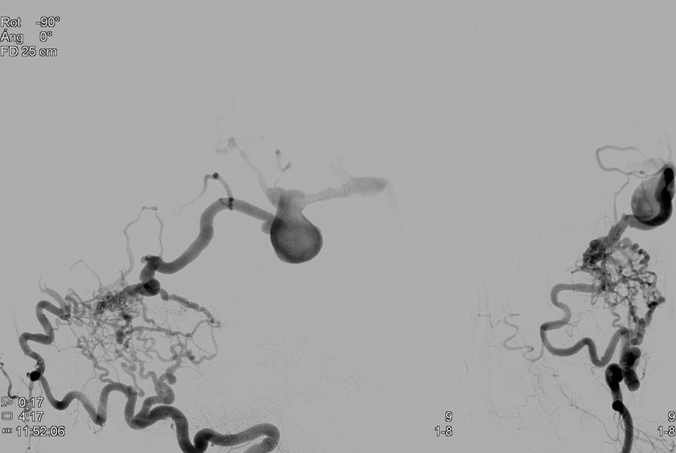

Se realiza arteriografía a las 12 horas del ingreso que muestra fístula arteriovenosa dural con aferencias arteriales de arteria occipital izquierda y drenaje a vena cortical temporal izquierda. Compatible con fístula dural Cognard tipo IV.

Podemos ver la visión lateral y AP en la figura 3:

Se decide proceder a realizar embolización de la fístula con la técnica de la olla Express para lo cual empleamos (Figura 4):